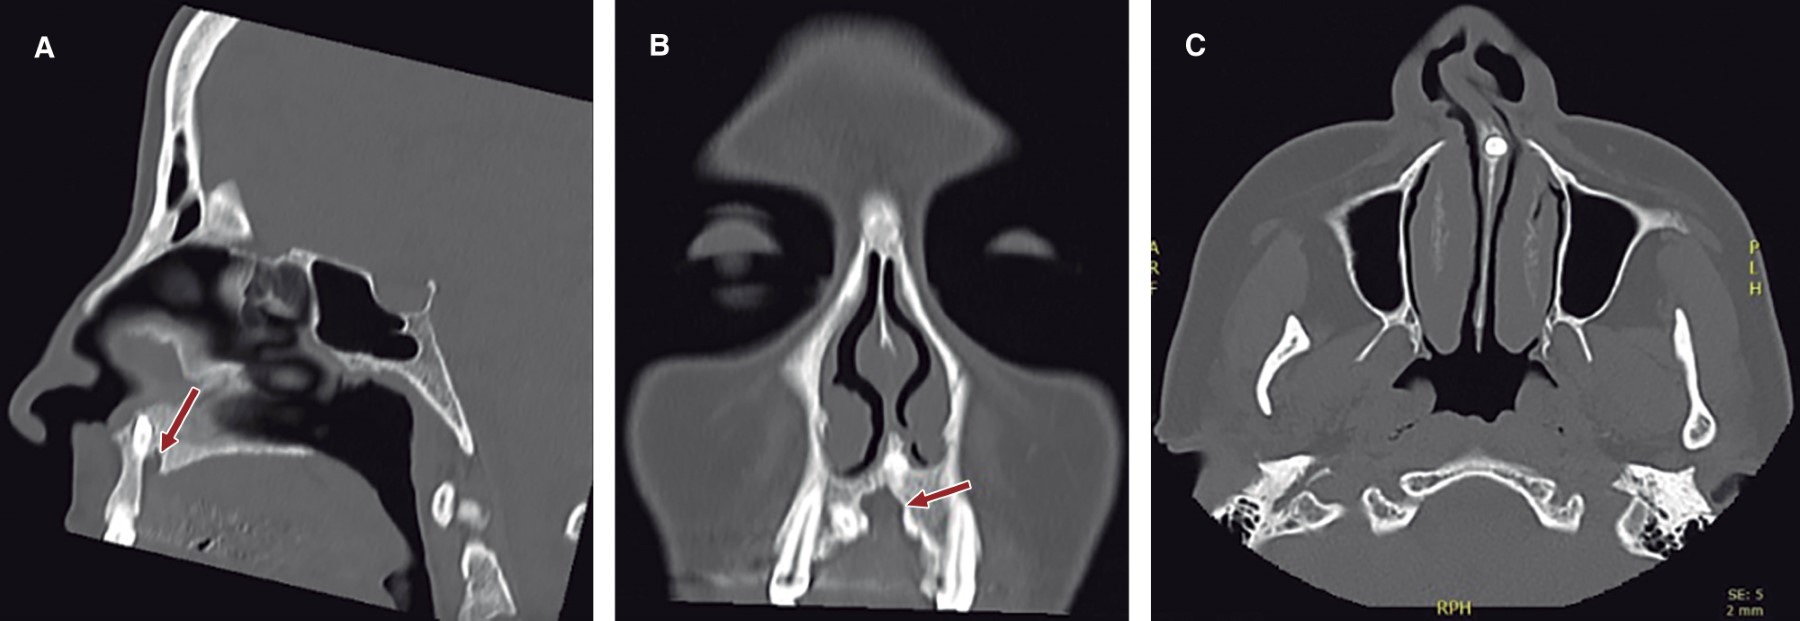

Al examen físico segmentario presenta septodesviación obstructiva/oclusiva anterior hacia fosa nasal derecha, con sospecha de secuelas de fractura de tabique anterior cartilaginoso, desviación de columela nasal hacia la derecha, laterorrinia a la derecha positiva e hipertrofia de cornetes. Es derivada a nuestro servicio maxilofacial por equipo de otorrinolaringología por hallazgo en tomografía computarizada previo a cirugía nasal funcional de dos dientes supernumerarios maxilares (Figura 1) y canal del nervio nasopalatino con un calibre considerablemente mayor a la norma (Figura 2). Uno de los dientes supernumerario es un mesiodens que se encuentra rotado, invertido con la cúspide hacia cefálico en el tabique nasal anterior y el otro en posición palatina en relación al canino superior izquierdo. Al examen clínico no se palpa mesiodens por cavidad oral ni cavidad nasal.

La fisura labio máxilo-palatina en microforma fue clasificado como defecto congénito en forma menor, microforma y minimicroforma según la extensión de la muesca de la unión bermellón-cutánea y la gravedad de la deformidad nasal por Yuzuriha y Mulliken.12 Se han informado fosas nasales colapsadas como una característica del labio hendido menor. Se supone que tales fosas nasales colapsadas son causadas por algunas anomalías en el tejido blando, como la ruptura del músculo orbicular de los labios.13 Con respecto al defecto óseo adyacente al canal nasopalatino (Figura 2A y 2B), dado el gran calibre y la pérdida de tejido óseo que se mantiene con los límites corticalizados y ausente de patología, se podría suponer la presencia de un defecto congénito incompleto de la unión de los procesos horizontales del maxilar, sospechando de alguna microforma de fisura labio máxilo-palatina.

Figura 2